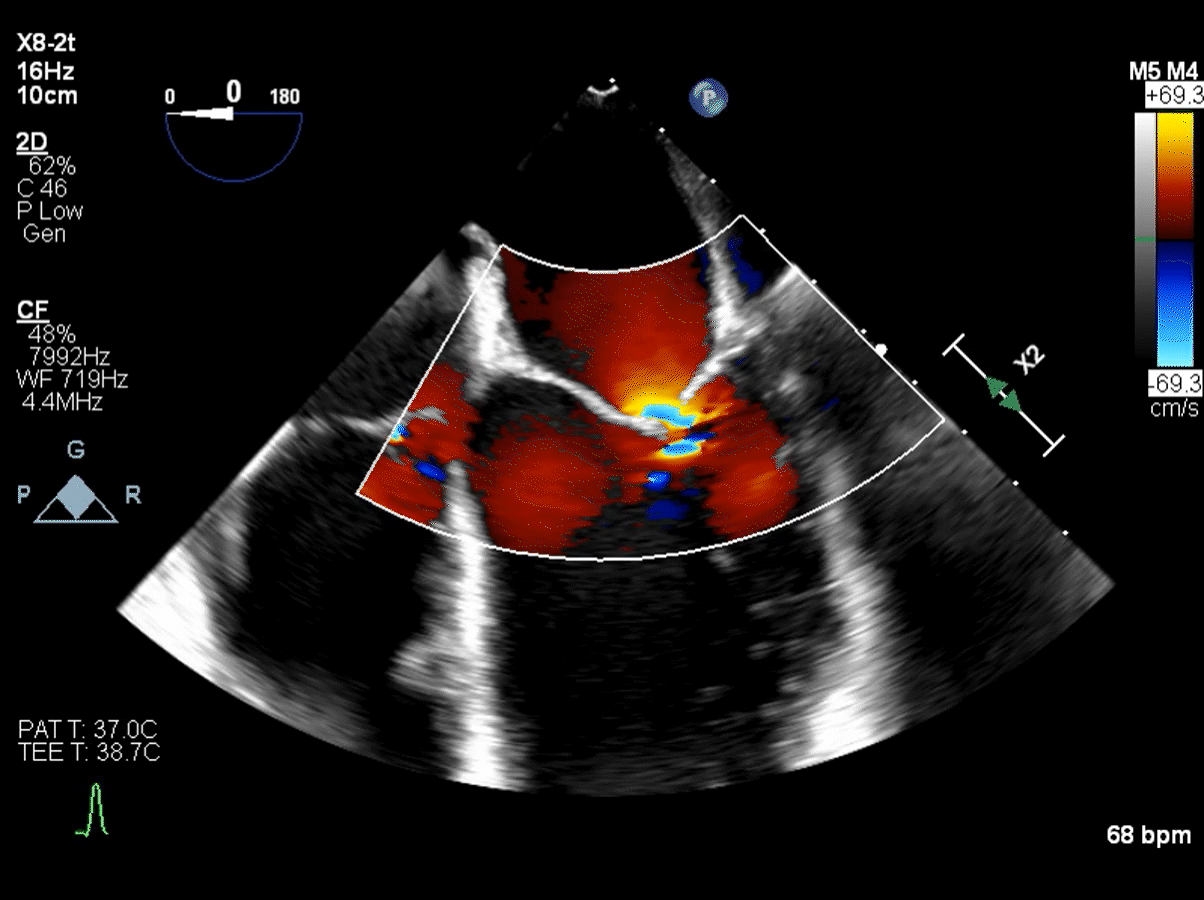

normal echocardiogram of mitral valve   echocardiogram of mitral valve with flail

With an echocardiogram, your doctor can “grade” the leak. Mitral valve regurgitation is typically graded on a scale from 0 to 4:

• 0 is no leak or very minor

• 1 is a mild leak

• 2 is a moderate leak

• 3 is a moderate to severe leak

• 4 is a severe leak

Most patients who need surgery have a grade 4 leak, or in some cases a grade 3. The valve may have a grade 2 leak for years, but it is not loud enough to be heard as a heart murmur.